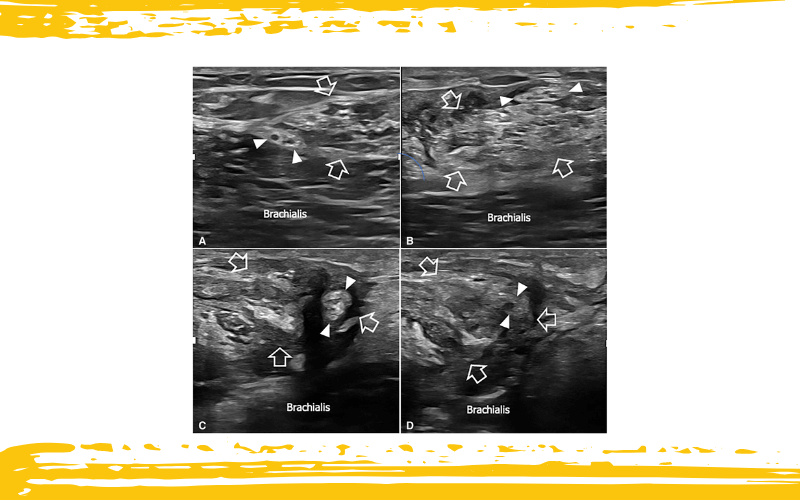

Neuropatía del nervio cutáneo lateral del antebrazo (LCNF) debido a atrapamiento posquirúrgico dentro del tendón del bíceps reparado.

Las imágenes (A, B, C y D) se obtuvieron mediante barrido de proximal a distal a lo largo del trayecto proximal del tendón del bíceps reparado (flechas delineadas) a los 30 días de la cirugía. El paciente fue remitido a evaluación ecográfica por persistencia de dolor urente y parestesias en la cara lateral del antebrazo tras la intervención.

En A, el LCNF (puntas de flecha blancas) aparece tumefacto pero permanece en su localización normal en el lado lateral de un tendón del bíceps notablemente aumentado de tamaño y heterogéneo.

En B y C, el LCNF se observa progresivamente traccionado—primero de forma superficial y posteriormente medial—en relación con el tendón del bíceps, hasta quedar completamente incluido y atrapado dentro del tejido fibrosado y degenerado del tendón, como se aprecia en D.